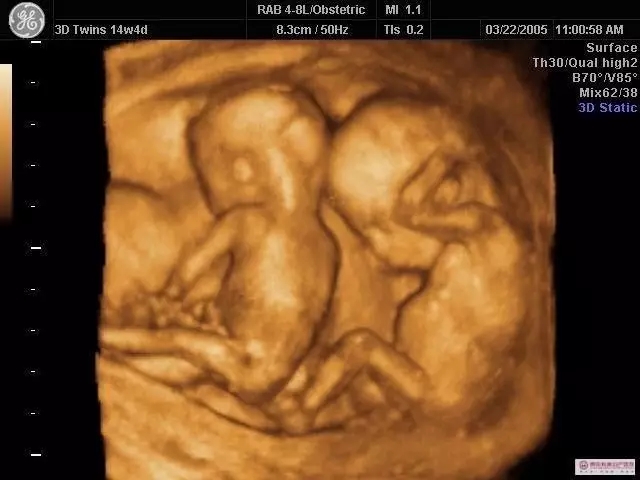

應(yīng)用領(lǐng)域:放射,CT,MRI等

應(yīng)用領(lǐng)域:超聲,各種光學(xué)窺鏡與電子鏡等